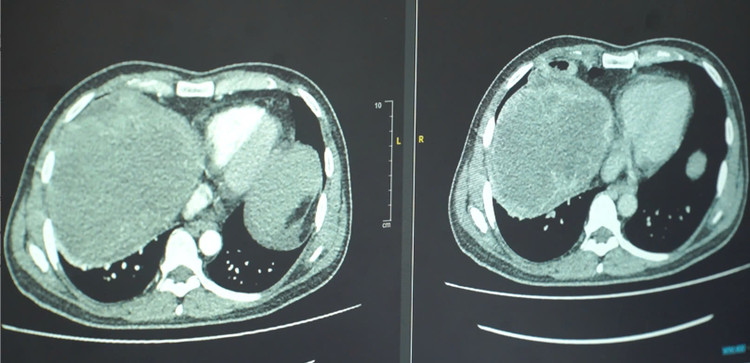

| Kết quả phim chụp khối u - Ảnh BVCC |

Kết quả ghi nhận người bệnh bị ung thư đại tràng di căn gan giai đoạn IV, kích thước khối u gan là 15cm, gan to xâm lấn xuống dưới vùng hố chậu. Tại thời điểm nhập viện, chức năng gan của bệnh nhân suy giảm mạnh, chỉ số men gan cao 250 UI/L, bilirubin tăng cao dẫn đến vàng da vàng mắt nhiều.